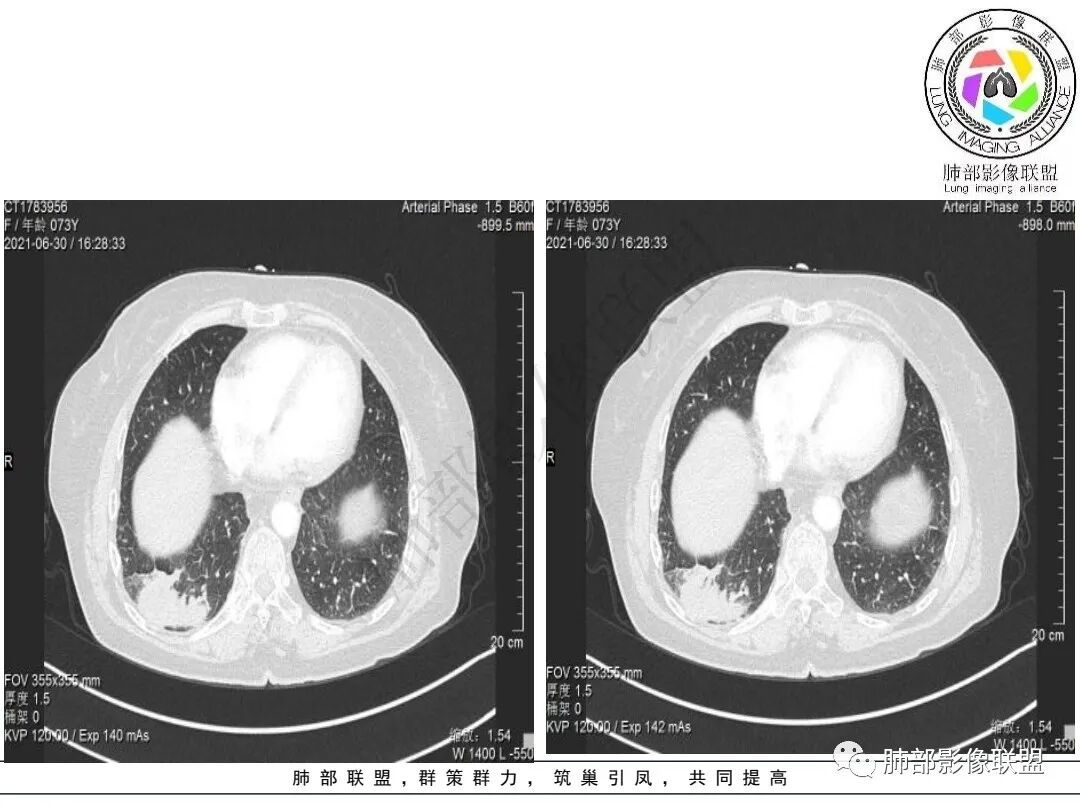

右肺下叶指套样高密度影,边界清楚,形态欠规则,累积多个叶段,平扫密度均匀,增强扫描不均匀强化,后纵隔淋巴结肿大,淋巴结内可见不均匀坏死,强化,女性,73岁,无实验室指标,考虑恶性:腺癌,鳞癌?神经内分泌癌(大细胞?),淋巴上皮瘤样癌。加一个转移瘤。

右肺下叶不规则形肿块,密度不均,轻度强化,纵隔肺门肿大淋巴结,里面血管好像破坏了,考虑恶性,鳞癌?鉴别结核。

右下肺肿块,多发浅分叶呈锯齿状,有指样突起和胸膜牵拉,不均匀强化,肿块内血管增粗模糊,后纵隔淋巴结肿大坏死融合呈冰冻状,定性恶性,低分化腺癌>小细胞肺癌。

老年女性,有桶状胸,长期吸烟?右肺下叶占位并纵膈7组,肺门10组淋巴结明显肿大融合,有不均匀性强化,肺内可见下叶支气管外压性狭窄,管腔近段感觉支气管没有影响,整体病灶成支气管走形,边界清楚,考虑恶性可能性大,小?

考虑小细,纵膈及右侧肺门淋巴结肿大并左下肺小叶间隔增厚,提示周围及中央淋巴管转移,左心房及左下肺静脉受累。

右肺下叶不规则肿块,纵隔及右侧肺门淋巴结肿大,不均匀强化,见坏死,考虑恶性,小细胞癌或鳞癌。

2.右肺下叶不规则实性密度块影,占据外后基底段及背段较大范围,可见轻度分叶、毛刺及棘状突起,未见明显胸膜牵拉及凹陷。

3.右肺下叶支气管轻度狭窄,病灶内见部分充气支气管征,外后基底段不能连续跟踪。

轻度不均匀强化,病灶内小血管显示不满意,未见明确坏死区。

4.右肺门及纵隔见多处增大淋巴结,不均匀环形强化,后下纵隔(隆突下)肿大淋巴结十分显眼!